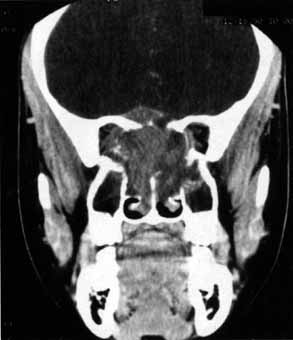

Visual field testing can also be helpful in diagnosis of orbital processes. Optic disc–associated visual field changes are usually altitudinal because of the structure of the horizontal raphé (Fig. 13). This visual field defect is typically a result of anterior ischemic optic neuropathy (AION).24 Compressive lesions of the orbit or retrobulbar inflammation are more likely to produce a central or cecocentral scotoma. However, one must be aware that there is a significant degree of overlap between various types of optic nerve lesions and visual field abnormalities.25 In these cases, neuroimaging may be a useful adjunct in differentiating between different neuro-ophthalmic and orbital processes.26

Fig. 13 Pathway of ganglion cell axons that originate temporal to the macula (A) do not cross the horizontal meridian. Any damage to the superior ganglion cell axons at the optic disc will generate atrophy within the superior nerve fiber layer (B). The visual field defect will be inferior but not crossing the horizontal plane. (Hoyt WF, Rios-Montenegro EN, Behrens MM, et al: Homonymous hemioptic hypoplasia: funduscopic features in standard and red-free illumination in three patients with congenital hemiplegia. Br J Ophthamol 56:537, 1972)